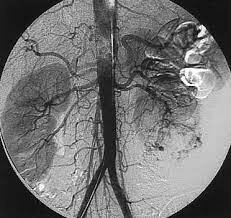

• Angiografía digital

Angiografía digital

En el 1981 apareció la angiografía digital que ha mejorado el estudio y tratamiento de las patologías vasculares.